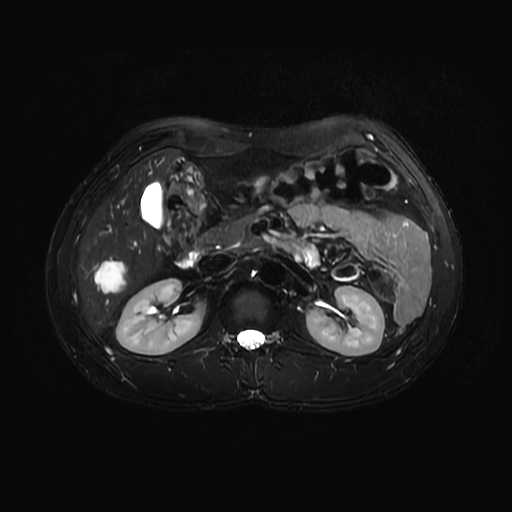

MRI検査

内科領域

腹部

肝血管腫

膵管内乳頭粘液性腫瘍(IPMN)